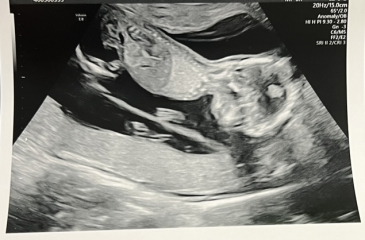

journeytomum · 26/04/2024 07:20

Hope everyone is going ok. I had a scan at 15+2 yesterday of the twins following the large sudden bleed last week. They still don't know where it came from but the twins are ok which is the main thing! I am still wiped from the pregnancy and finding it very hard going with a toddler.

Any guesses on genders from the scan pics?!

OCTOBER 2024 BABIES - Thread 4

AppleTree16 · 26/04/2024 08:54

Glad to hear it wasn’t a twin!

I think you’ve got a girl and boy there? But my nub experience is just guesswork!